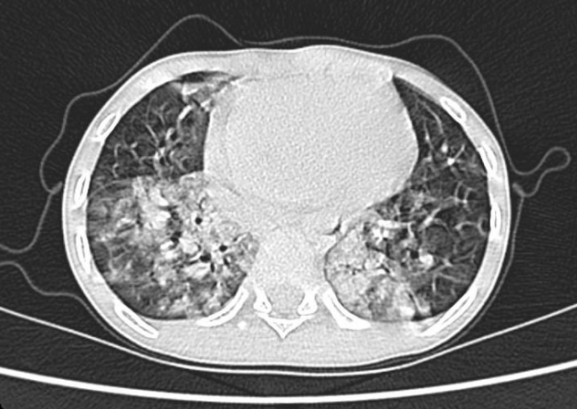

隨著冬季流感高發(fā)期的到來(lái),兒童呼吸道感染病例顯著增多。貴陽(yáng)市公共衛(wèi)生救治中心重癥醫(yī)學(xué)科(大營(yíng)路院區(qū))近日成功救治了一名危重癥甲流患兒,經(jīng)過(guò)長(zhǎng)達(dá)24天的全力搶救與精心護(hù)理,孩子最終轉(zhuǎn)危為安,康復(fù)出院。 這名6歲患兒因持續(xù)高熱、呼吸急促被緊急送醫(yī)。入院時(shí),患兒體溫高達(dá)40℃,血氧飽和度僅80%,胸部CT顯示雙肺多處感染病灶,病情急速進(jìn)展,生命垂危。 時(shí)間就是生命。重癥醫(yī)學(xué)科陳佳主任帶領(lǐng)醫(yī)療團(tuán)隊(duì)迅速研判,果斷為患兒實(shí)施氣管插管,并啟動(dòng)俯臥位通氣、支氣管鏡灌注等關(guān)鍵治療。護(hù)理團(tuán)隊(duì)24小時(shí)不間斷監(jiān)測(cè)生命體征,精細(xì)化氣道管理,積極預(yù)防并發(fā)癥,同時(shí)給予患兒心理安撫與親情式陪伴。 在醫(yī)療與護(hù)理團(tuán)隊(duì)的緊密協(xié)作下,患兒熬過(guò)了最危險(xiǎn)的階段,肺部感染逐漸吸收,順利脫離呼吸機(jī),身體各項(xiàng)機(jī)能穩(wěn)步恢復(fù)。出院當(dāng)天,患兒家屬將一面錦旗送到醫(yī)護(hù)人員手中,眼中含淚連聲道謝。這面錦旗,不僅代表著一個(gè)家庭的感激,更是對(duì)醫(yī)護(hù)團(tuán)隊(duì)專(zhuān)業(yè)堅(jiān)守與生命至上的深深認(rèn)可。 溫馨提示:冬季是流感高發(fā)期,請(qǐng)注意做好個(gè)人防護(hù),保持室內(nèi)通風(fēng),勤洗手,必要時(shí)接種流感疫苗,同時(shí)也提醒廣大家長(zhǎng),流感高發(fā)季節(jié),若孩子出現(xiàn)持續(xù)高熱、呼吸急促、精神萎靡等癥狀,須及時(shí)就醫(yī)。